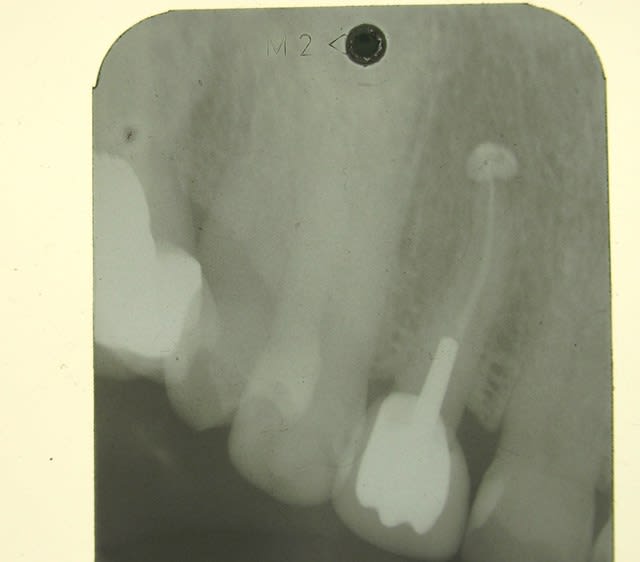

11/12/2015 à 12h29

controle du cas de la page 19 , ce jour .

faut aimer l'aspect champignon , mais ça va , chance !!!!

11.12 - Eugenol

oui ca avance... enfin.....tu aurais dû sous-exposer la rx encore un chouia et là on aurait dit que c'est carémment cicatrisé.

voilà ,j'ai repris la photo de la meme radio , ce qui ne change pas le fait qu'elle soit tjs sur l'arcade :-)